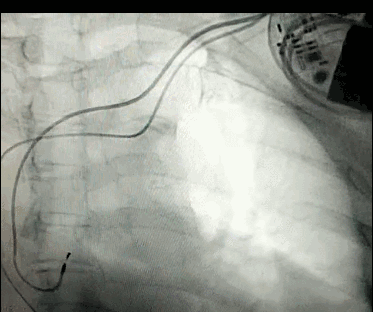

腦血管成像的“金標(biāo)準(zhǔn)”!——DSA三部曲之技術(shù)篇

DSA是將造影劑注入需要檢查的血管中,使血管顯露原形,然后通過(guò)系統(tǒng)處理,使血管顯示更加清晰,便于醫(yī)生診斷或進(jìn)行手術(shù)。